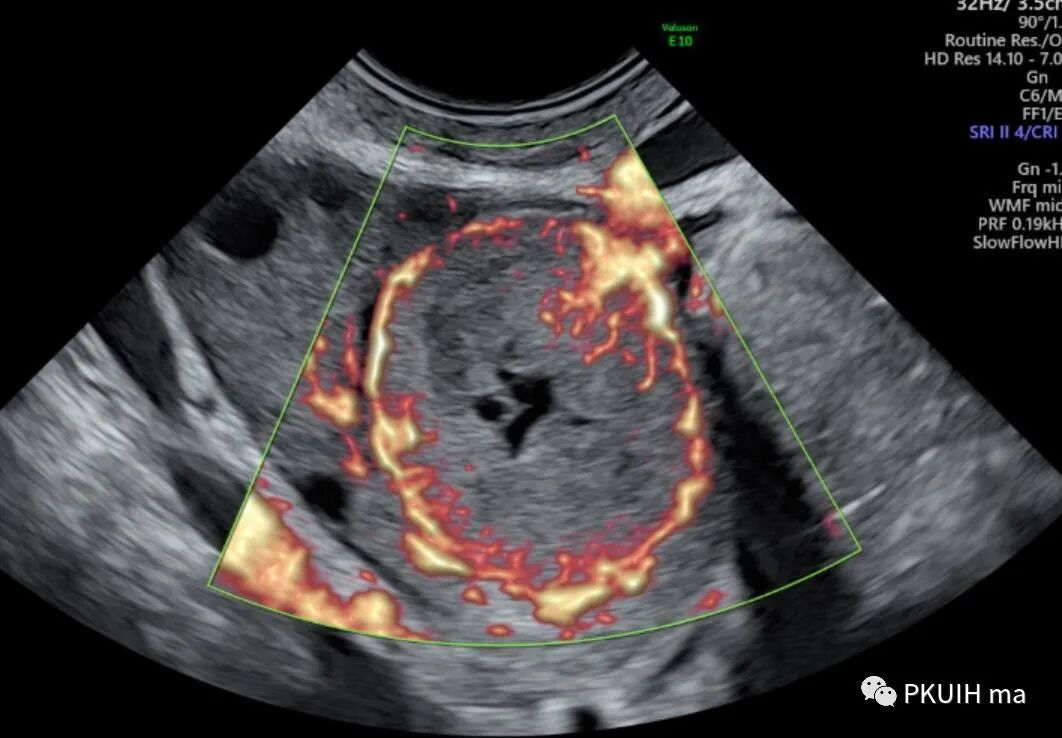

同样我们可以把这个功能用在妇科方面,评估内膜血流情况,可以借助三维来对内膜血流分级。

还有也可以借助此功能来观察卵巢肿物内的血流,对鉴别良恶性及囊实性有一定帮助。